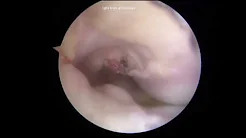

Meniscal Allograft Transplantation made simple A how to guide PART 1